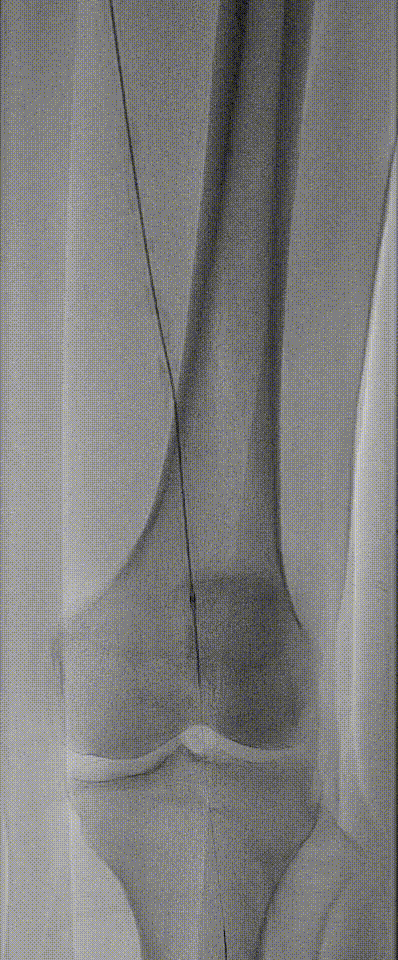

图:DA 造影+通过病变

图:IVUS确认

图:Hawk Plus 切除斑块

图:IN.PACT DCB 6-250 扩张,最终造影